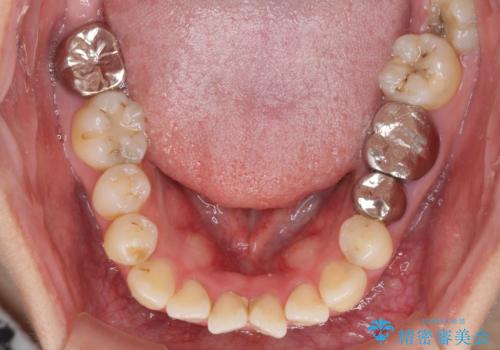

- 八重歯と前歯のデコボコ、開咬を気にして来院された患者様です。

抜歯矯正が必要であることはご自身で理解されており、目立たない装置をご希望であったので、上顎が裏側装置であるハーフリンガル装置にて治療を行うこととしました。

上顎前歯や下顎大臼歯に根管治療の必要な歯がいくつかあるため、矯正治療と並行して根管治療を行い、その後オールセラミッククラウンにて補綴治療を行うこととしました。